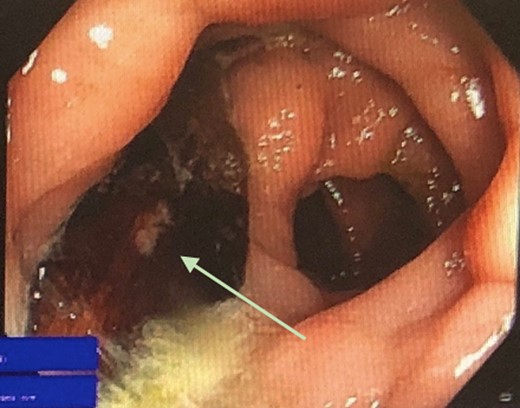

The patient was admitted to hospital and commenced on intravenous antibiotics. The following day he underwent a flexible sigmoidoscopy, which demonstrated multiple small and large diverticulum in the sigmoid colon. A foreign body was found in the sigmoid colon at 28 cm from the anal verge, suggestive of ingested bone (Fig. 2). The foreign body appeared to be lodged within a diverticulum. Adjacent to this, was a localized area of moderately inflamed mucosa, possibly reactive to the foreign body. No obvious entero-colonic fistula was identified. Biopsies were taken of this inflamed area, which later demonstrated on histopathology to be consistent with non-specific reactive changes. The foreign body was retrieved successfully endoscopically using tripod forceps (Fig. 3).

Colonoscopic view of foreign object within segment of sigmoid diverticulosis.